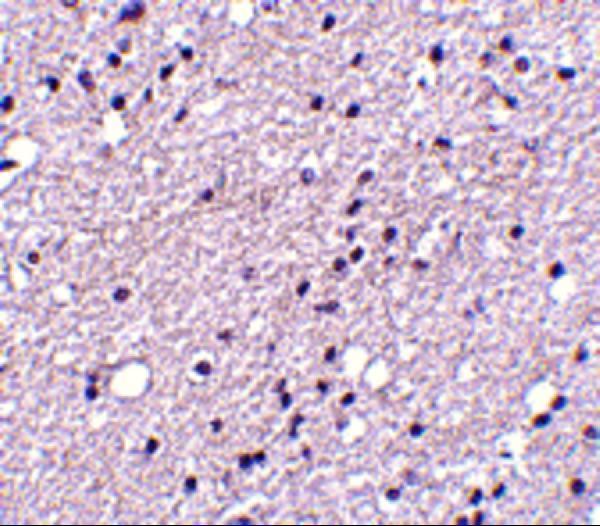

Facts about Neuromedin-K receptor.

The rank order of affinity of the receptor to tachykinins is: neuromedin-K > substance K > substance P. .

Neurokinin B Receptor; neurokinin beta receptor; Neuromedin-K Receptor; NK-3 receptor; NK3R; NK-3R; NK3RMGC148061; NKR; TAC3R; TAC3RL; tachykinin receptor 3MGC148060; TACR3